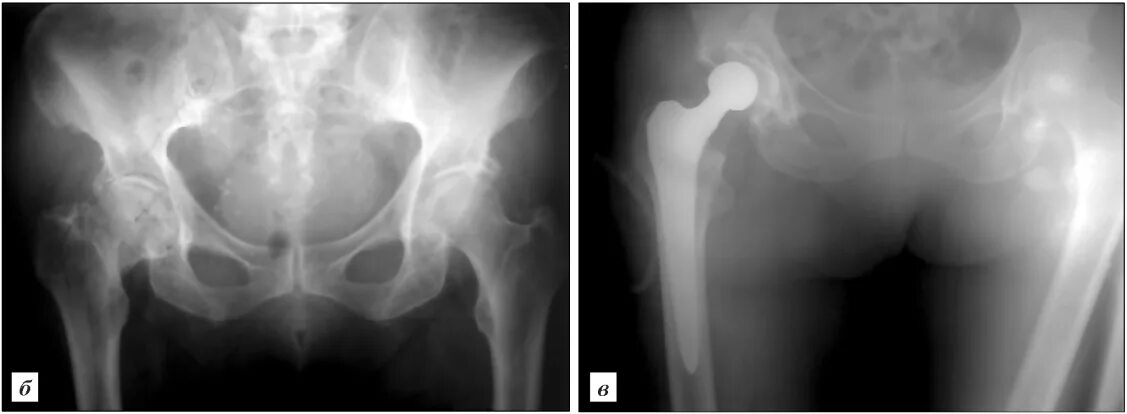

Как определить перелом шейки бедра у пожилых